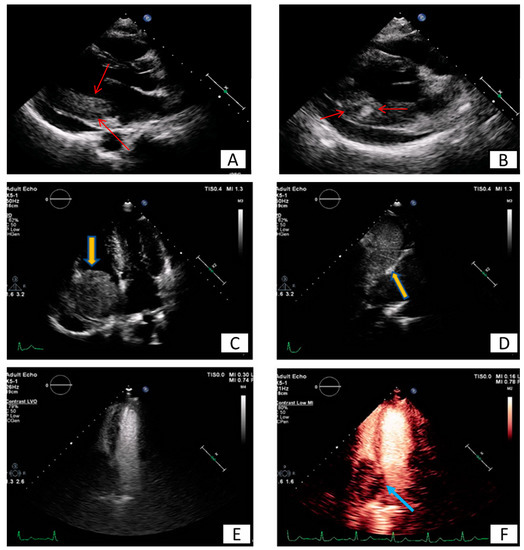

3.1. Transthoracic Echocardiography

3.2. Transesophageal Echocardiography